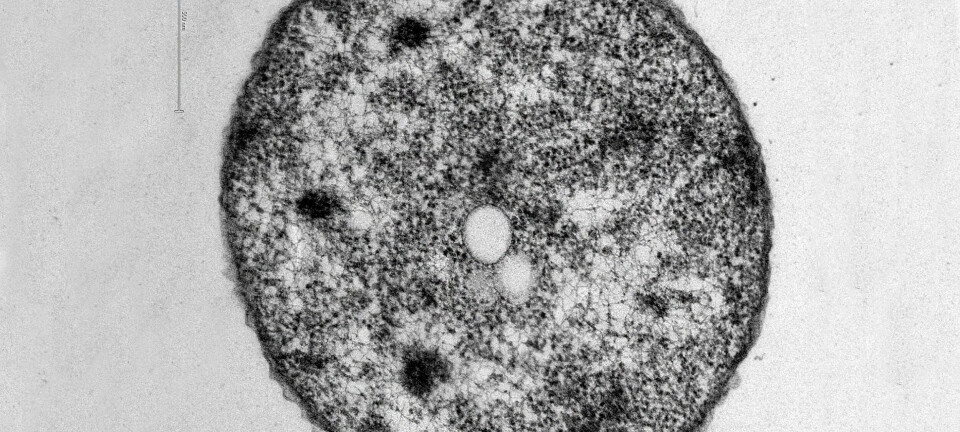

Científicos chilenos descubrieron que las quinonas inhiben el crecimiento de Piscirickettsia salmonis in vitro sin producir efectos celulares negativos.

Bajo este enfoque, científicos de la Universidad de Santiago de Chile y la Universidad Santo Tomás investigaron el efecto de varios compuestos derivados de la 6-bromo-7-arilaminoisoquinolina-5,8-quinonas para inhibir el crecimiento de P. salmonis en condiciones de cultivo celular.

Los resultados indicaron que varias de las quinonas sintetizadas lograron reducir significativamente la viabilidad de la bacteria, sin producir citotoxicidad a ninguna de las concentraciones evaluadas, lo que abre la puerta a nuevos tratamientos farmacológicos para controlar esta enfermedad, que actualmente representa una de las principales causas de mortalidad en la salmonicultura.

“La infectividad de P. salmonis después del tratamiento con los compuestos análogos indicó que los derivados metil 6-bromo-7-((4-metoxifenil)amino)-1,3-dimetil-5,8-dioxo-5,8-dihidroisoquinolina-4-carboxilato (4b) y metil 7-((4′-amino-[1,1′-bifenil]-4-il)amino)-6-bromo-1,3-dimetil-5,8-dioxo-5,8-dihidroisoquinolina-4-carboxilato (4g) redujeron la carga bacteriana a una concentración de 25 μg/mL”, explicaron los autores.